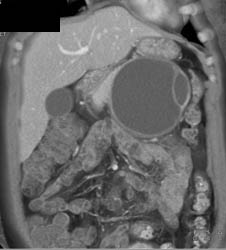

Islet Cell Tumor With Cavernous Transformation of the Portal Vein (CTPV) and Splenic Vein Occlusion